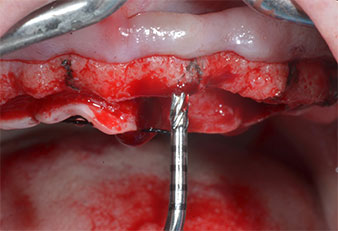

Ein flammenförmiges, diamantiertes piezochirurgisches Instrument (Piezomed I1) wurde verwendet, um die Implantatpositionen zu markieren und die Pilotpräparationen durchzuführen (Abb. 3). Dabei wurde darauf geachtet, eine Auf- und Abbewegung mit reduzierter Leistung, voller Spülung und niedrigem Druck (unter 300 g) anzuwenden. Als Nächstes wurde ein Pilotinstrument (Piezomed I2A/I2P) zur initialen Erweiterung der Implantatlager auf einen Durchmesser von 2 mm verwendet (Abb. 4), gefolgt von einem 3-mm-Instrument (Abb. 5).

Abb. 3: Die Präparation mit dem Ultraschallmarkerinstrument Piezomed I1 erfolgt mit einer Auf- und Abbewegung, parallel zur Längsachse des Arbeitsteils.

Abb. 5: Der abschließende Durchmesser wird mit den Instrumenten Piezomed I3A/I3P erreicht. Die Implantatlager für die 10-mm-Implantate an Position 11 und 21 werden mit einem Implantatmotor (Implantmed) mit einem 3,5-mm-Spiralbohrer fertiggestellt.

Abb. 4: Der nächste Schritt ist die initiale Erweiterung mit den Instrumenten Piezomed I2A/I2P, die in einer horizontalen Drehbewegung verwendet werden.

Wegen des relativ harten Knochens (D2) an den Positionen 11 und 21 wurden die 10 mm langen Implantatlager in diesem Bereich abschließend mit einem 4-mm-Spiralbohrer, dem chirurgischen Winkelstück WS-75 L von W&H und dem W&H Implantmed Implantologiemotor in Verbindung mit dem optionalen W&H Osstell ISQ module präpariert. Im Gegensatz dazu wurde der weiche Knochen der Implantatlager im Seitenzahnbereich mit dem Piezomed I3P auf den abschließenden Durchmesser von 3 mm erweitert. Die Implantate wurden dann transgingival eingesetzt, die Einheildauer betrug drei Monate (Abb. 6-10). Die vorhandene Prothese wurde auf vier provisorischen Implantaten abgestützt (Abb. 8).